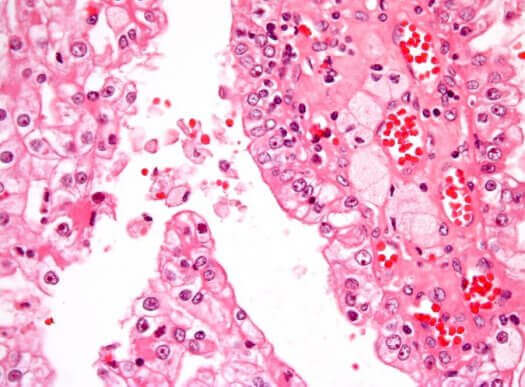

Lasten yleisin munuaissyöpä on Wilmsin kasvain, eli nefroblastooma, johon liittyy sikiön munuaissoluja muistuttavien solujen epänormaali lisääntyminen. Kaikista lasten kiinteistä kasvaimista noin 7 % ovat nefroblastoomia. Näitä kasvaimia todetaan eniten 1-5-vuotiailla lapsilla, ja tautia esiintyy yhtä paljon molemmilla sukupuolilla. 5-10 % tapauksista kasvain kehittyy kumpaankin munuaiseen.